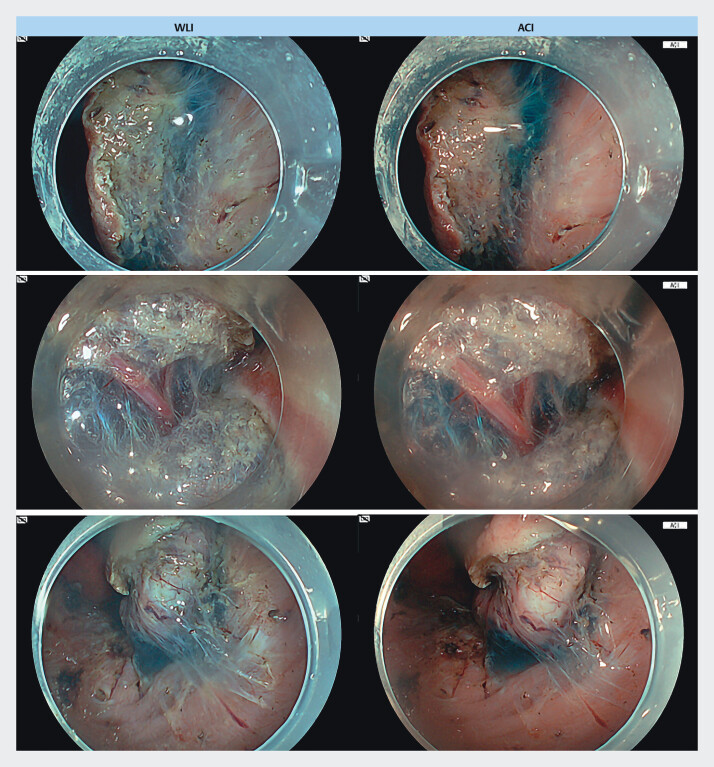

Background and study aims: Local injection of a small amount of blue dye into the submucosa can facilitate recognizing the dissection line in endoscopic submucosal dissection (ESD). Amber-red color imaging (ACI), which hardly affects the submucosal blue color, is suitable for the entire ESD. This study aimed to clarify characteristics of ACI during ESD.

Patients and methods: Nine endoscopic images were selected during submucosal dissection in four cases of gastric ESD to evaluate endoscopic ACI and white light imaging (WLI). Visibility of the dissection line and the submucosal vessel were evaluated by eight endoscopists using a 5-point Likert scale. The blue submucosal area of each endoscopic image and color signal surrounding the submucosa were compared between ACI and WLI. In addition, the color signals in gradient dilutions of blue solutions were compared in ex vivo experiments.

Results: Visibility of the dissection line was better in ACI than in WLI and visibility of the submucosal vessels was slightly better in ACI. The size ratio of the blue area in ACI and WLI (i.e., ACI/WLI) ranged from 0.53 to 0.65, indicating that the blue area in the ACI was narrower. The red signal intensity of the surroundings with respect to the submucosa was greater in ACI than in WLI, which was related to the narrower blue area in ACI. Ex vivo experiments corroborated this observation.

Conclusions: ACI highlights the submucosa in blue only where sufficient solution is injected, which facilitates recognition of the dissection line during ESD.